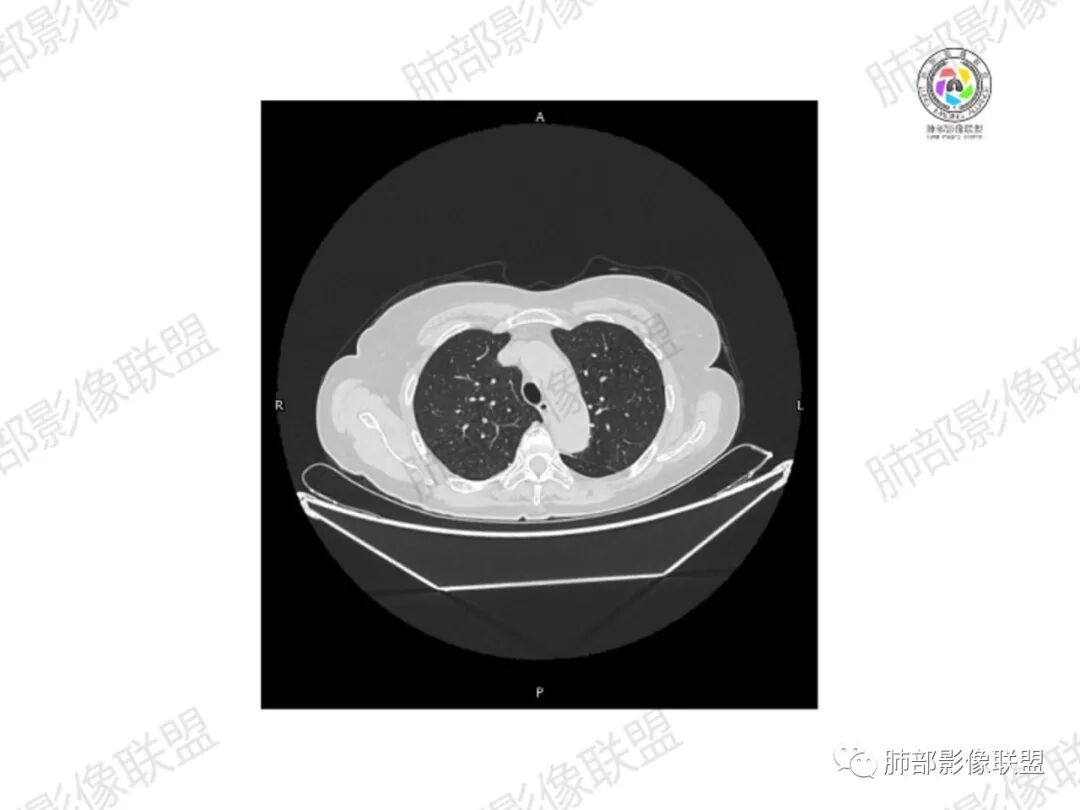

5.双肺多发类圆形结节影,边界清楚,随机分布,其间多见钙化密度影。

6.双肺门及纵隔未见肿大淋巴结。

3.双肺病灶符合转移瘤,伴有中央部分钙化者也以骨肉瘤转移较为多见。